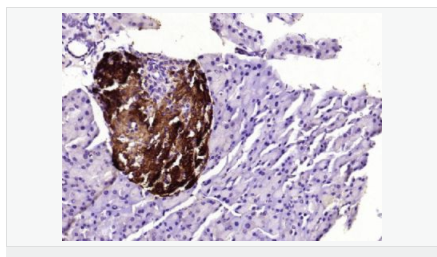

| 產(chǎn)品應(yīng)用 | WB=1:500-2000 ELISA=1:5000-10000 IHC-P=1:100-500 IHC-F=1:100-500 ICC=1:100-500 IF=1:100-500 (石蠟切片需做抗原修復) not yet tested in other applications. optimal dilutions/concentrations should be determined by the end user. |

| 產(chǎn)品介紹 | This gene encodes an aldo-keto reductase that catalyzes the NADPH-dependent reduction of pteridine derivatives and is important in the biosynthesis of tetrahydrobiopterin (BH4). Mutations in this gene result in DOPA-responsive dystonia due to sepiaterin reductase deficiency. A pseudogene has been identified on chromosome 1. [provided by RefSeq, Jul 2008] Function: Catalyzes the final one or two reductions in tetra-hydrobiopterin biosynthesis to form 5,6,7,8-tetrahydrobiopterin. Subunit: Homodimer. Subcellular Location: Cytoplasm. Post-translational modifications: In vitro phosphorylation of Ser-213 by CaMK2 does not change kinetic parameters. DISEASE: Defects in SPR are the cause of dystonia DOPA-responsive due to sepiapterin reductase deficiency (DRDSPRD) [MIM:612716]. In the majority of cases, patients manifest progressive psychomotor retardation, dystonia and spasticity. Cognitive anomalies are also often present. The disease is due to severe dopamine and serotonin deficiencies in the central nervous system caused by a defect in BH4 synthesis. Dystonia is defined by the presence of sustained involuntary muscle contractions, often leading to abnormal postures. Similarity: Belongs to the sepiapterin reductase family. SWISS: P35270 Gene ID: 6697 Database links: Entrez Gene: 6697 Human Omim: 182125 Human SwissProt: P35270 Human Unigene: 301540 Human Important Note: This product as supplied is intended for research use only, not for use in human, therapeutic or diagnostic applications. |